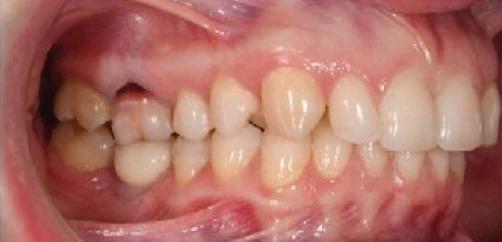

Пациентът постъпи в моята клини ка с наличие на темпоромандибуларен дисфункционален болков синдром, едно странно изместен диск с редукция в дяс ната става, клас II, подклас 2, тесни гор на и долна челюст със струпване, дъл бок овърбайт

и гингивална усмивка. Започнахме лечението с пълна диагно стика (анамнеза, интраорални, екстра

7Dental Tribune Bulgarian Edition / октомври 2022 г. Преди лечението Фиг. 1 Фиг. 4 Фиг. 7 Фиг. 10 Фиг. 13 Фиг. 16 Фиг. 17 Фиг. 18 Фиг. 19 Фиг. 20 Фиг. 11 Фиг. 14 Фиг. 12 Фиг. 15 Фиг. 8 Фиг. 9 Фиг. 5 Фиг. 6 Фиг. 2 Фиг. 3